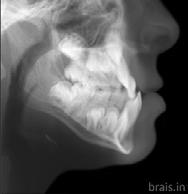

Estudios radiográficos de inicio en la radiografía lateral de cráneo (Figu ra 5) tenemos la clase II esquelética con un ANB de 7°, hiperdivergencia, aumento de la altura facial anterior, disminución de la altura facial poste rior y proclinación del incisivo supe rior con 1 a plano palatino de 121° e incisivo inferior de 1 a plano mandi bular de 99°.

En la radiografía panorámica (Figu ra 6) se observan 32 dientes, con los terceros molares en formación, adicionalmente la molar 46 con una